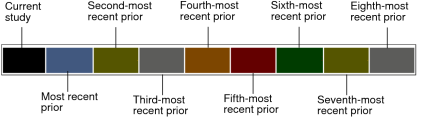

Black represents the current study and dark blue represents the most recent prior study. Prior studies are represented by a repeating sequence of five colors.